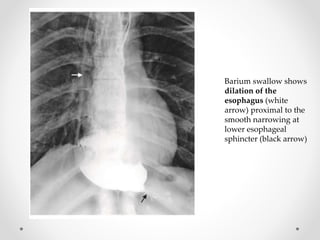

Barium swallow shows

dilation of the

esophagus (white

arrow) proximal to the

smooth narrowing at

lower esophageal

sphincter (black arrow)

Barium swallow shows dilationof the esophagus (white arrow) proximal to the smooth narrowing at lower esophageal sphincter (black arrow)